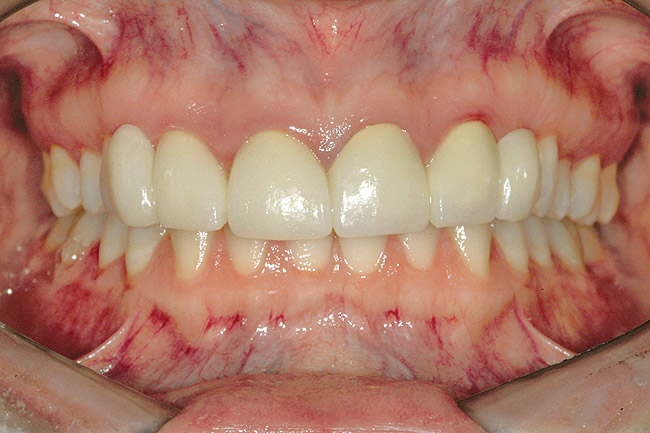

Fig 29 (through Fig 32). Jackscrews were activated 0.5 mm/day after 5-day latency period. Note pure translation of segments without tipping. Result 8 months postsurgery. Tooth No. 12 was converted to a canine, and an implant was placed in regenerate bone. Note amount of alveoloskeletal correction and increase in volume of maxillary arch. Also note the amount of protraction of maxillary anterior segments while anchorage was maintained in posterior segment. Restorative dentist: Michael E. Carter, DDS.

Fig 30. Jackscrews were activated 0.5 mm/day after 5-day latency period. Note pure translation of segments without tipping. Result 8 months postsurgery. Tooth No. 12 was converted to a canine, and an implant was placed in regenerate bone. Note amount of alveoloskeletal correction and increase in volume of maxillary arch. Also note the amount of protraction of maxillary anterior segments while anchorage was maintained in posterior segment. Restorative dentist: Michael E. Carter, DDS.

Figure 30

Fig 31. Jackscrews were activated 0.5 mm/day after 5-day latency period. Note pure translation of segments without tipping. Result 8 months postsurgery. Tooth No. 12 was converted to a canine, and an implant was placed in regenerate bone. Note amount of alveoloskeletal correction and increase in volume of maxillary arch. Also note the amount of protraction of maxillary anterior segments while anchorage was maintained in posterior segment. Restorative dentist: Michael E. Carter, DDS.

Figure 31

Fig 32. Jackscrews were activated 0.5 mm/day after 5-day latency period. Note pure translation of segments without tipping. Result 8 months postsurgery. Tooth No. 12 was converted to a canine, and an implant was placed in regenerate bone. Note amount of alveoloskeletal correction and increase in volume of maxillary arch. Also note the amount of protraction of maxillary anterior segments while anchorage was maintained in posterior segment. Restorative dentist: Michael E. Carter, DDS.